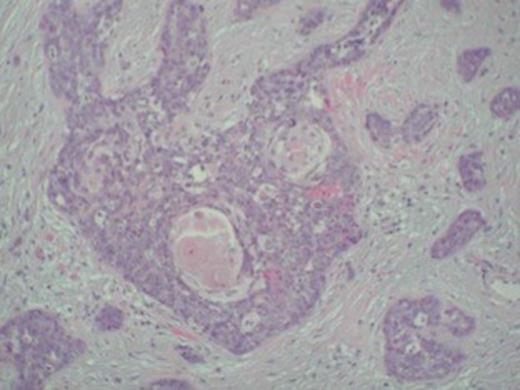

Squamous cell carcinoma metastasis infiltrating peritoneal fat and serosa evident of right hemicolectomy specimen

Despite an initial response to treatment, four months later, the patient presented with clinical picture suggestive of large bowel obstruction. An explorative laparotomy unveiled a large mass involving the terminal ileum and caecum along with dense adhesions of ileocaecal loops. A 4 cm nodule in the right lobe of liver was also discovered. The patient underwent right hemicolectomy with an end-to-end ileocolic anastomosis. The surgical specimen consisted of 21 and 15 cm length of small and large bowel, respectively. The central 10 cm of the bowel was of undeterminable nature due to its tortuous nature caused by innumerable adhesions. The mucosa was unremarkable except for focal oedema. Histological examination showed poorly-differentiated squamous cell carcinoma infiltrating serosa with prominent intravascular spread. The tumour was predominantly confined to the peritoneal fat and serosa with no obvious invasion of the muscularis, submucosal, and mucosal layers (Figure 1 and 2). The appearance was consistent with metastatic spread from primary anal lesion. Unfortunately, the patient did not recover and died from multiple organ failure on the fourth post-operative day.

Keratin pearls confirming squamous cell carcinoma metastasis in the tumour specimen